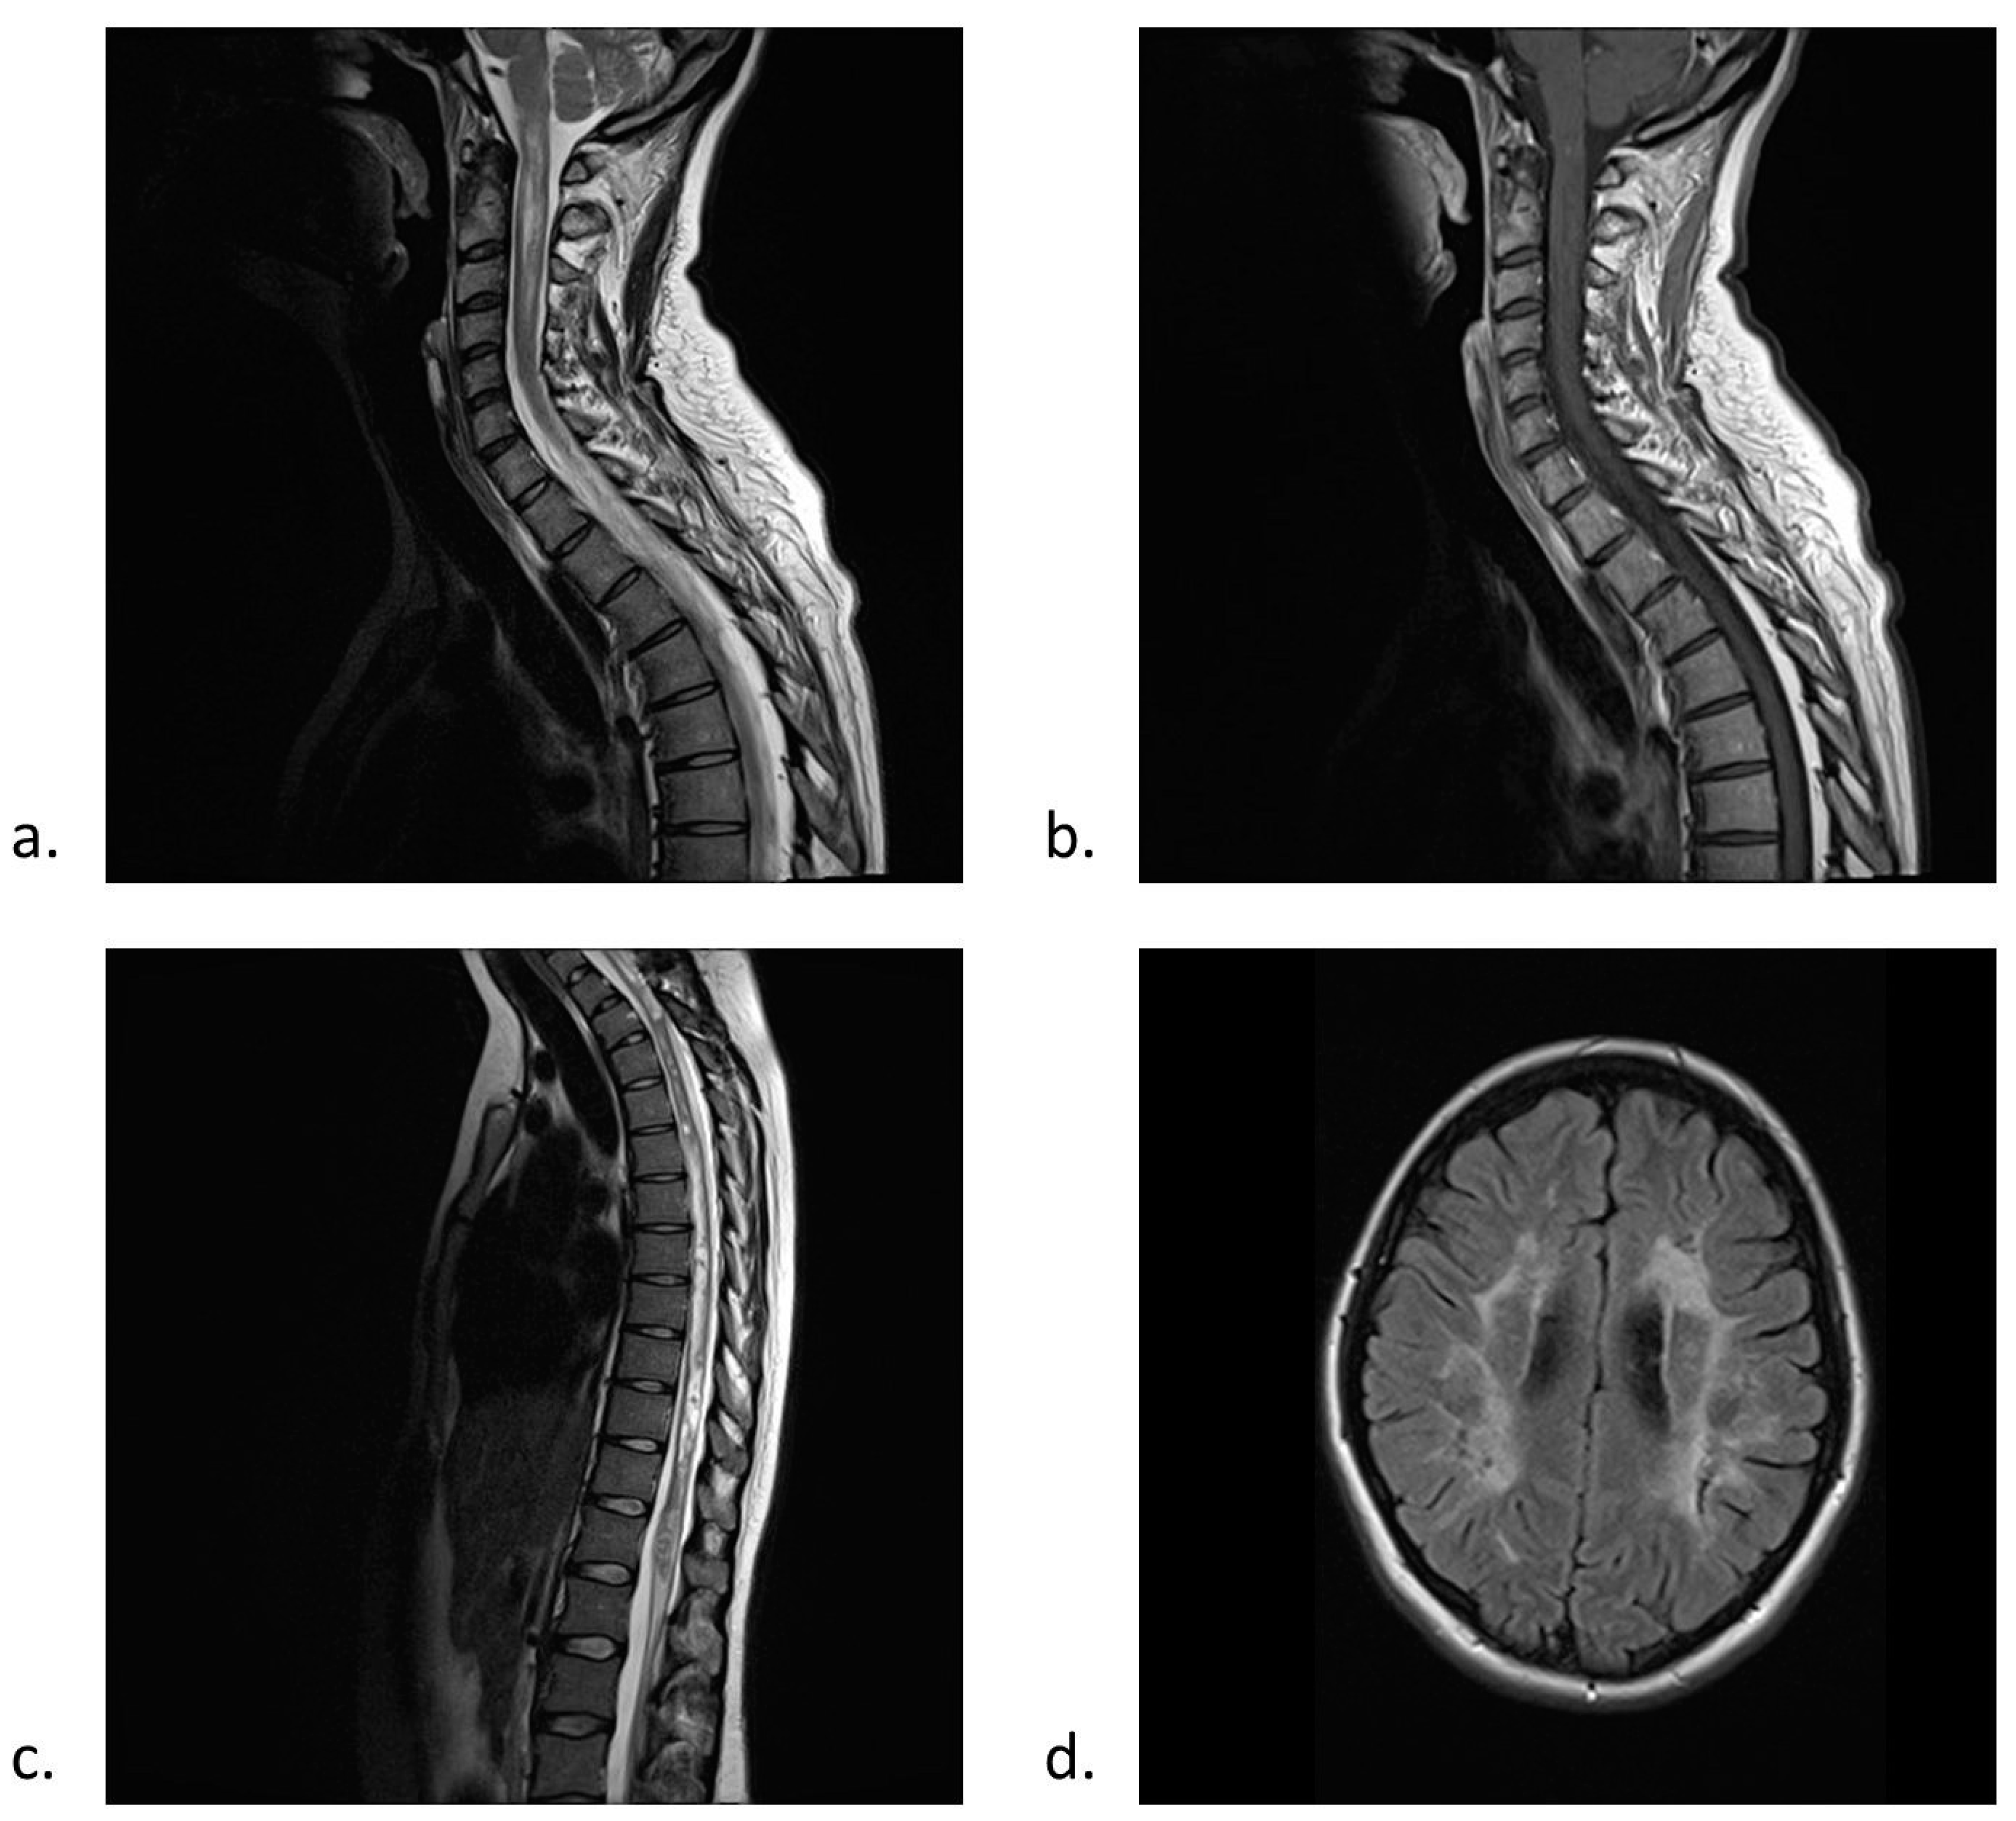

1.3. Diagnostic Criteria for NMO and NMO Spectrum Disorders (NMOsd)

1.4. Clinical Features and Laboratory Findings